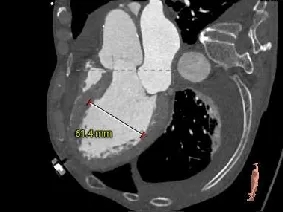

主动脉根部测量

Annulus

24.7mm

VR图

SOV:

41.0*40.9*47.6mm

STJ:

39.1mm

AAO:

40.1mm